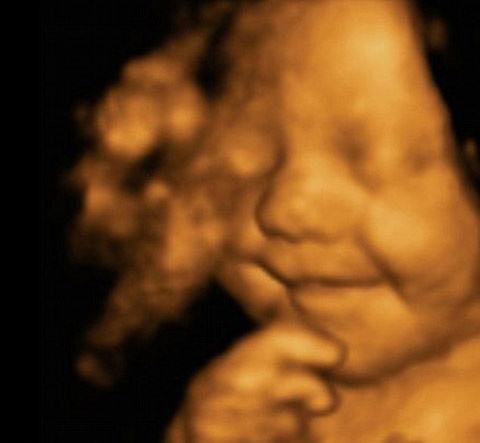

Grinning from ear to ear, this picture shows little Leo Hargreaves was rather happy with his world – even before he was born.

The remarkable image was taken from an ultrasound scan at 31 weeks.

The image is a 4D scan - increasingly popular with expectant parents to get a glimpse of how their child will look.

Rather then the grainy ‘flat’ images produced by the 2D scanners usually used by the NHS, a 4D machine stitches together pictures taken from a variety of angles to create clear three-dimensional images.

These are then recorded on video – the fourth dimension.

照片上這位名叫里奧?哈格里夫斯(Leo Hargreaves)的小寶貝還未出生就已經(jīng)咧著嘴笑個(gè)不停,一臉幸福的樣子。

這張與眾不同的照片來(lái)自于超聲波掃描,當(dāng)時(shí)里奧才31周大。

圖像由4D掃描采集。這項(xiàng)技術(shù)越來(lái)越受準(zhǔn)爸爸準(zhǔn)媽媽的歡迎,他們迫不及待地想要一窺自家孩子的模樣。

英國(guó)國(guó)民保健服務(wù)(NHS)通常使用2D掃描,由此拍出的圖像是平面點(diǎn)狀物,而4D掃描則將多角度拍攝而成的圖片拼接在一起組成清晰的三維圖像。

這第四個(gè)維度就是寶寶在母親肚子里的一舉一動(dòng)被記錄成像。